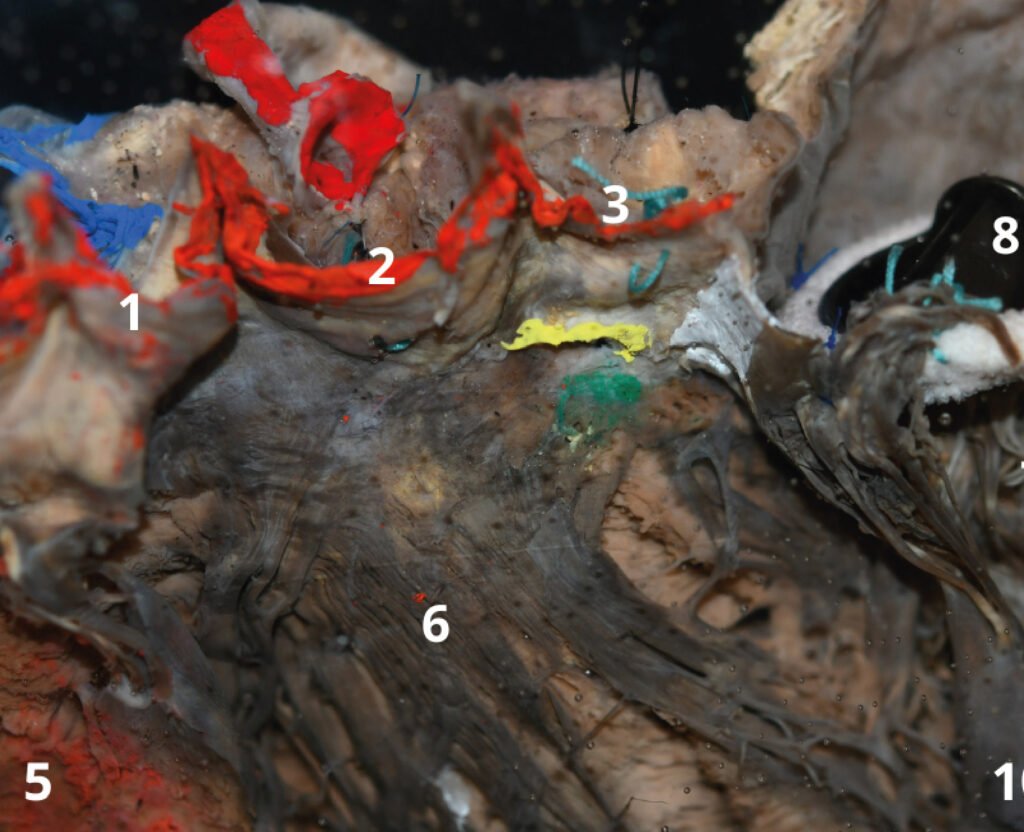

Museo.

Encontrarás los preparados de nuestro laboratorio en el museo de Anatomía J. J. Naón, Facultad de Medicina, Universidad de Buenos Aires, con su descripción.

Encontrarás los preparados de nuestro laboratorio en el museo de Anatomía J. J. Naón, Facultad de Medicina, Universidad de Buenos Aires, con su descripción.